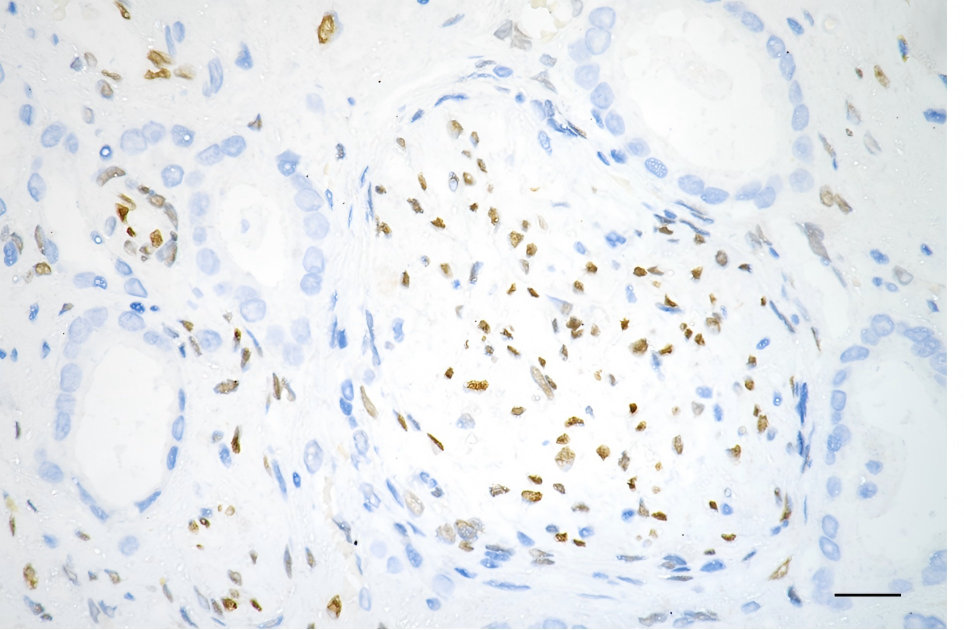

在视网膜病变中,FGF2既参与组织修复,也与病理性血管生成密切相关。缺氧条件下,YY1乳酸化可增强FGF2转录并促进血管新生 [7];PIK3IP1下调和miRNA-15a/16-1簇缺失也均可通过不同机制提升FGF2相关信号,推动异常血管生成 [8,9]。与此同时,A1-PEG则可通过提升FGF2表达,在抑制病理性新生血管形成的同时促进血管修复和视网膜功能改善 [10]。这表明FGF2在神经和视网膜疾病中具有明显的双重性,其作用方向高度依赖具体病理背景。